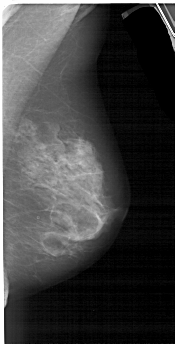

A_1553_1.RIGHT_MLO

RIGHT_MLO LINES 5146 PIXELS_PER_LINE 2611 BITS_PER_PIXEL 12 RESOLUTION 43.5 NON_OVERLAY